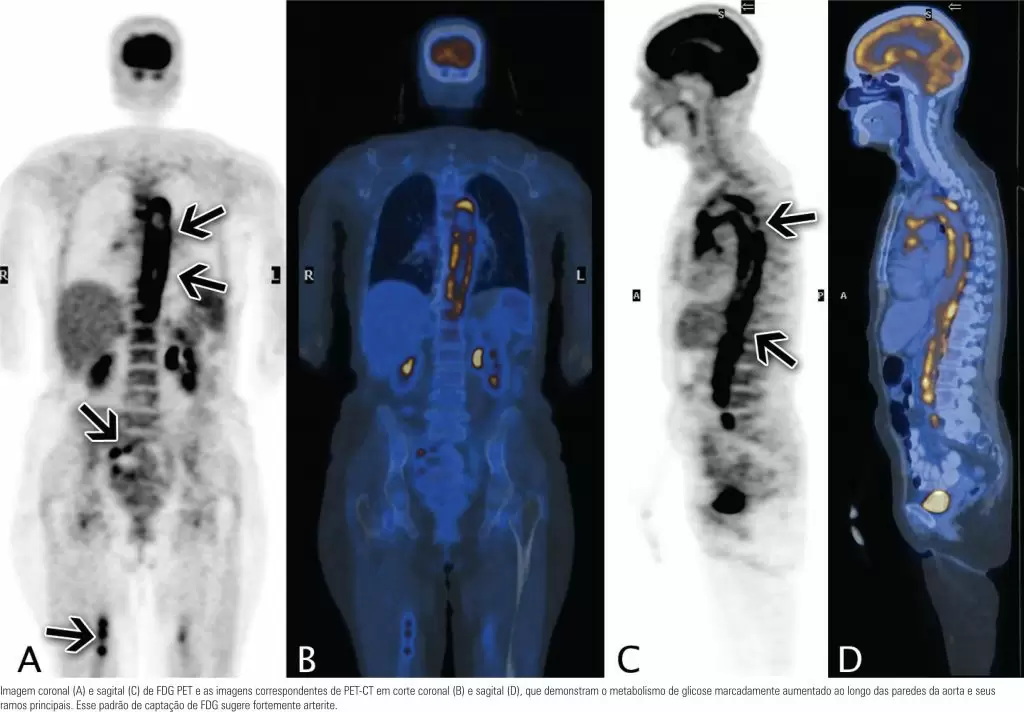

Paciente do sexo feminino, branca, 69 anos, encaminhada ao Departamento de Radiologia para investigação de febre de origem indeterminada (FOI), fadiga por sete meses e início recente de dor torácica atípica. Os exames laboratoriais mostraram níveis séricos elevados de proteína C-reativa e velocidade de hemossedimentação.

A fusão de tomografia com emissão de pósitrons e tomografia computadorizada (PET-CT) com F18-fluorodeoxiglicose (FDG) foi realizada para avaliar a FOI e excluir alguma doença maligna. As imagens com FDG mostraram uma captação muito aumentada, difusa e circunferencial, que sugeria um processo inflamatório difuso ao longo das paredes da aorta e das artérias subclávias.